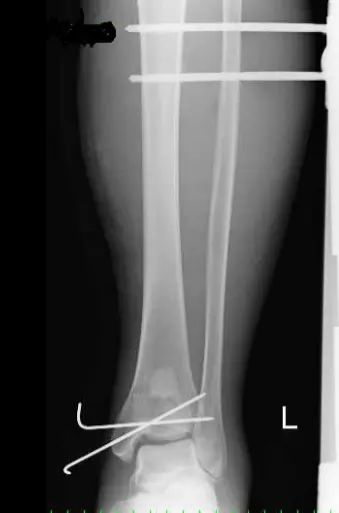

本症例は受傷直後に軟部組織の損傷を強く認め(足関節周囲は軟部組織が非常に薄い)、一期的なORIFは困難な状態であった。本症例のように軟部組織の損傷を強く認める状態でのORIFは感染、皮膚壊死といった問題が生じる危険性がある。そのため、軟部組織の回復まで一時的に鋼線牽引療法(traction)や創外固定術を施行し、軟部組織の炎症・腫脹が回復してきた後にORIF(two stage surgery)を施行する。

創外固定は、Ligamentotaxisにより骨折部や関節面の間接的整復と軟部組織の早期回復のためにtwo stage surgeryに頻用される。

Ligamentotaxis:伸延力(distraction forces)を加えることにより骨折部周囲の靱帯や筋肉に張力が働き、骨折部を間接的に整復することである。

創外固定法は、Ⅰ.開放骨折、Ⅱ.皮下骨折、Ⅲ.多発外傷、Ⅳ.関節内骨折、Ⅴ.骨または軟部組織の欠損、Ⅵ.創外固定を用いた間接的整復、などに用いられる。利点は、①骨の血流を温存できる、②軟部組織への障害が少ない、③手技が簡便で時間がかからない、④間接的整復と整復位の調整が可能、⑤感染巣や汚染創を介さずにスクリューを挿入し整復固定できる、⑥骨延長と変形の矯正が可能、などが挙げられる。

短所・注意点は、①スクリュー刺入部の感染、②フレームが煩わしく整容上の問題、③スクリュー刺入孔を通じた骨折、④創外固定除去後の再骨折、⑤神経血管刺貫、⑥筋または腱刺貫、⑦遷延治療、⑧区画症候群、⑨装置が高価、⑩コンプライアンスの悪い患者では器具調整が困難、などがある。

関節内骨折の治療目標は、完全な関節面の再建と骨片間の圧迫により受傷前の状態に機能を戻すことである。そのためORIFを行うが、軟部腫脹が著しく早期にORIFを施行できない場合には創外固定術を施行する。本症例も腫脹が著しく、感染や皮膚壊死の危険があり創外固定術を行った。創外固定術は軟部組織保護のための一時的な処置で、通常1~2週間後に最終的なORIFを行い、本症例も創外固定術後14日目にORIFを施行した。